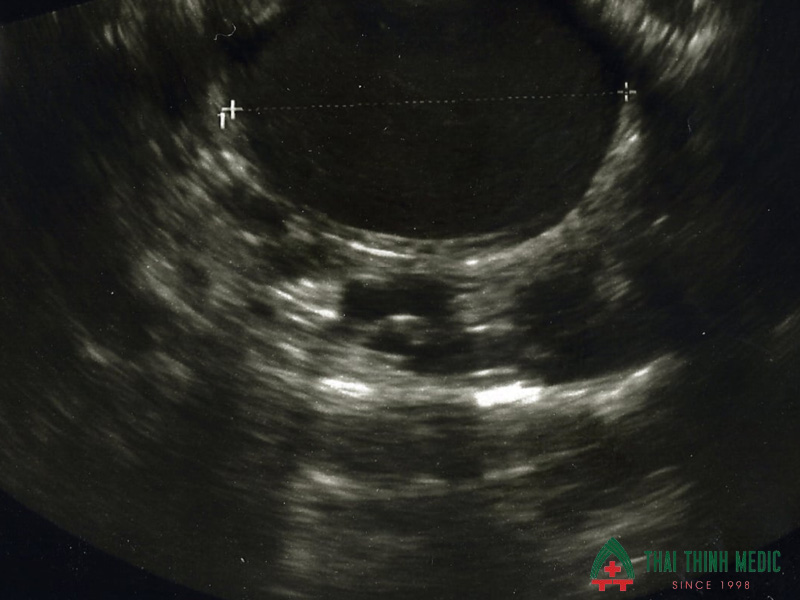

- U nang lạc nội mạc buồng trứng là dấu hiệu thường gặp và dễ nhận biết nhất của lạc nội mạc tử cung trên siêu âm. Hình ảnh điển hình là một hoặc nhiều nang buồng trứng chứa dịch đặc, đồng nhất, có dạng kính mờ hoặc echo hỗn hợp, thành nang thường dày và đều. U nang này thường tồn tại dai dẳng qua nhiều chu kỳ kinh, khác với nang cơ năng thông thường.

Hình ảnh lạc nội mạc tử cung trên siêu âm